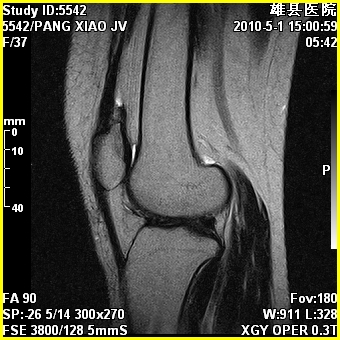

右股骨下端前内侧类圆形异常信号,位于干骺端,呈长t1长t2改变,但信号不均,t1图上病灶中心见小片状稍高信号影,t2图上见散在稍低信号影,stir像呈高信号,因病灶较小,缺乏特征性改变,结合患者年龄及部位,考虑嗜酸性肉芽肿可能性大。胫骨关节面下的小囊状异常信号,如果一元论考虑则为嗜酸性肉芽肿,不过发生在这个部位的少见,二元论考虑为邻关节骨囊肿。半月板与前后交叉韧带均未见异常。